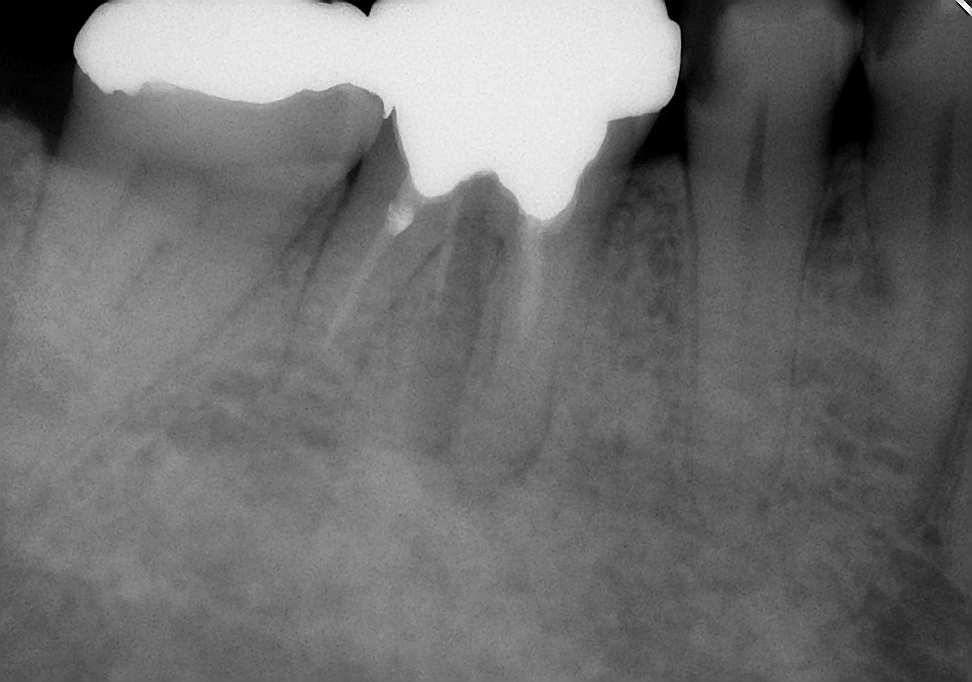

↑7ヵ月後

初診時に溶けていた骨もだいぶ再生されてきました。7ヶ月間症状も特になく、気にすることなく左右バランスよく咬めるとの事。ということで、主治医の先生でかぶせ物を入れてもらうことにしました。まずは一安心(^o^)